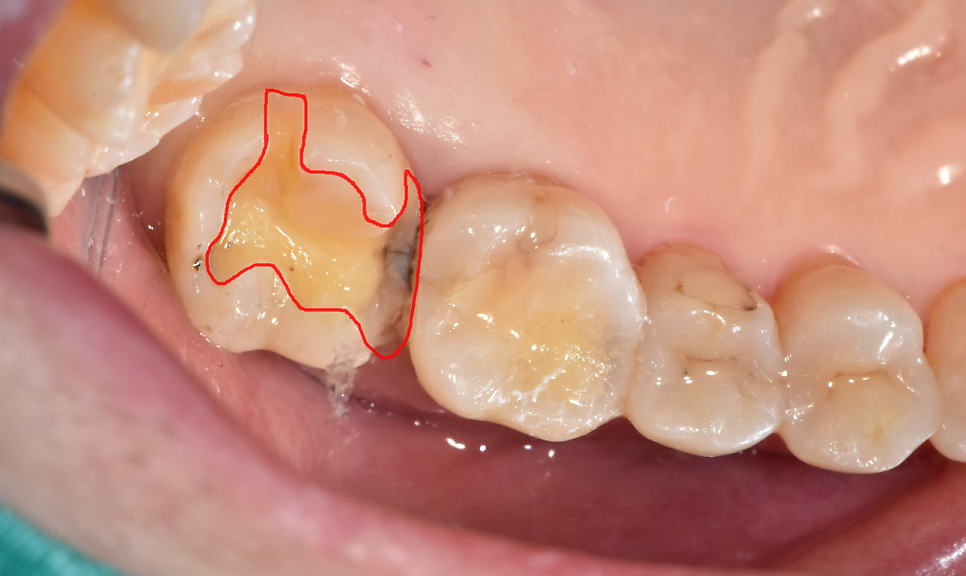

230708

옆 부위가 썩었어도

기구 접근이 가능한 위에서부터 충치 부위를 제거하니

숨겨져 있던 속살이 보이네요~

안쪽이 까만게 눈으로 확인되었습니다.